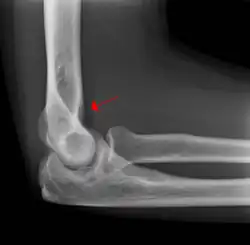

Fat pad sign

The fat pad sign, also known as the sail sign, is a potential finding on elbow radiography which suggests a fracture of one or more bones at the elbow. It may indicate an occult fracture that is not directly visible. Its name derives from the fact that it has the shape of a spinnaker (sail).[1] It is caused by displacement of the fat pad around the elbow joint. Both anterior and posterior fat pad signs exist, and both can be found on the same X-ray.

The fat pad sign is invaluable in assessing for the presence of an intra-articular fracture of the elbow. An anterior fat pad is often normal. However a posterior fat pad seen on a lateral x-ray of the elbow is always abnormal. The patient will be unable to flex their elbow and requires orthopaedic input.[2]